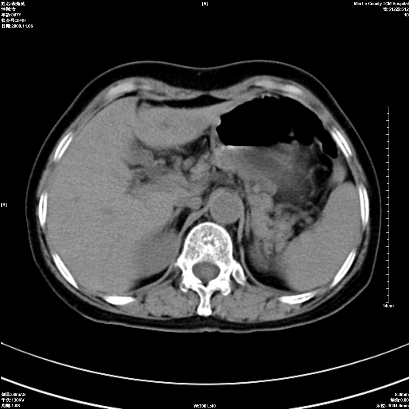

以下是引用卜一在2008-11-6 15:58:00的发言:[br]胰头略增大,胆总管扩张,末端渐行性狭窄。多考虑:胰头癌!建议增强!